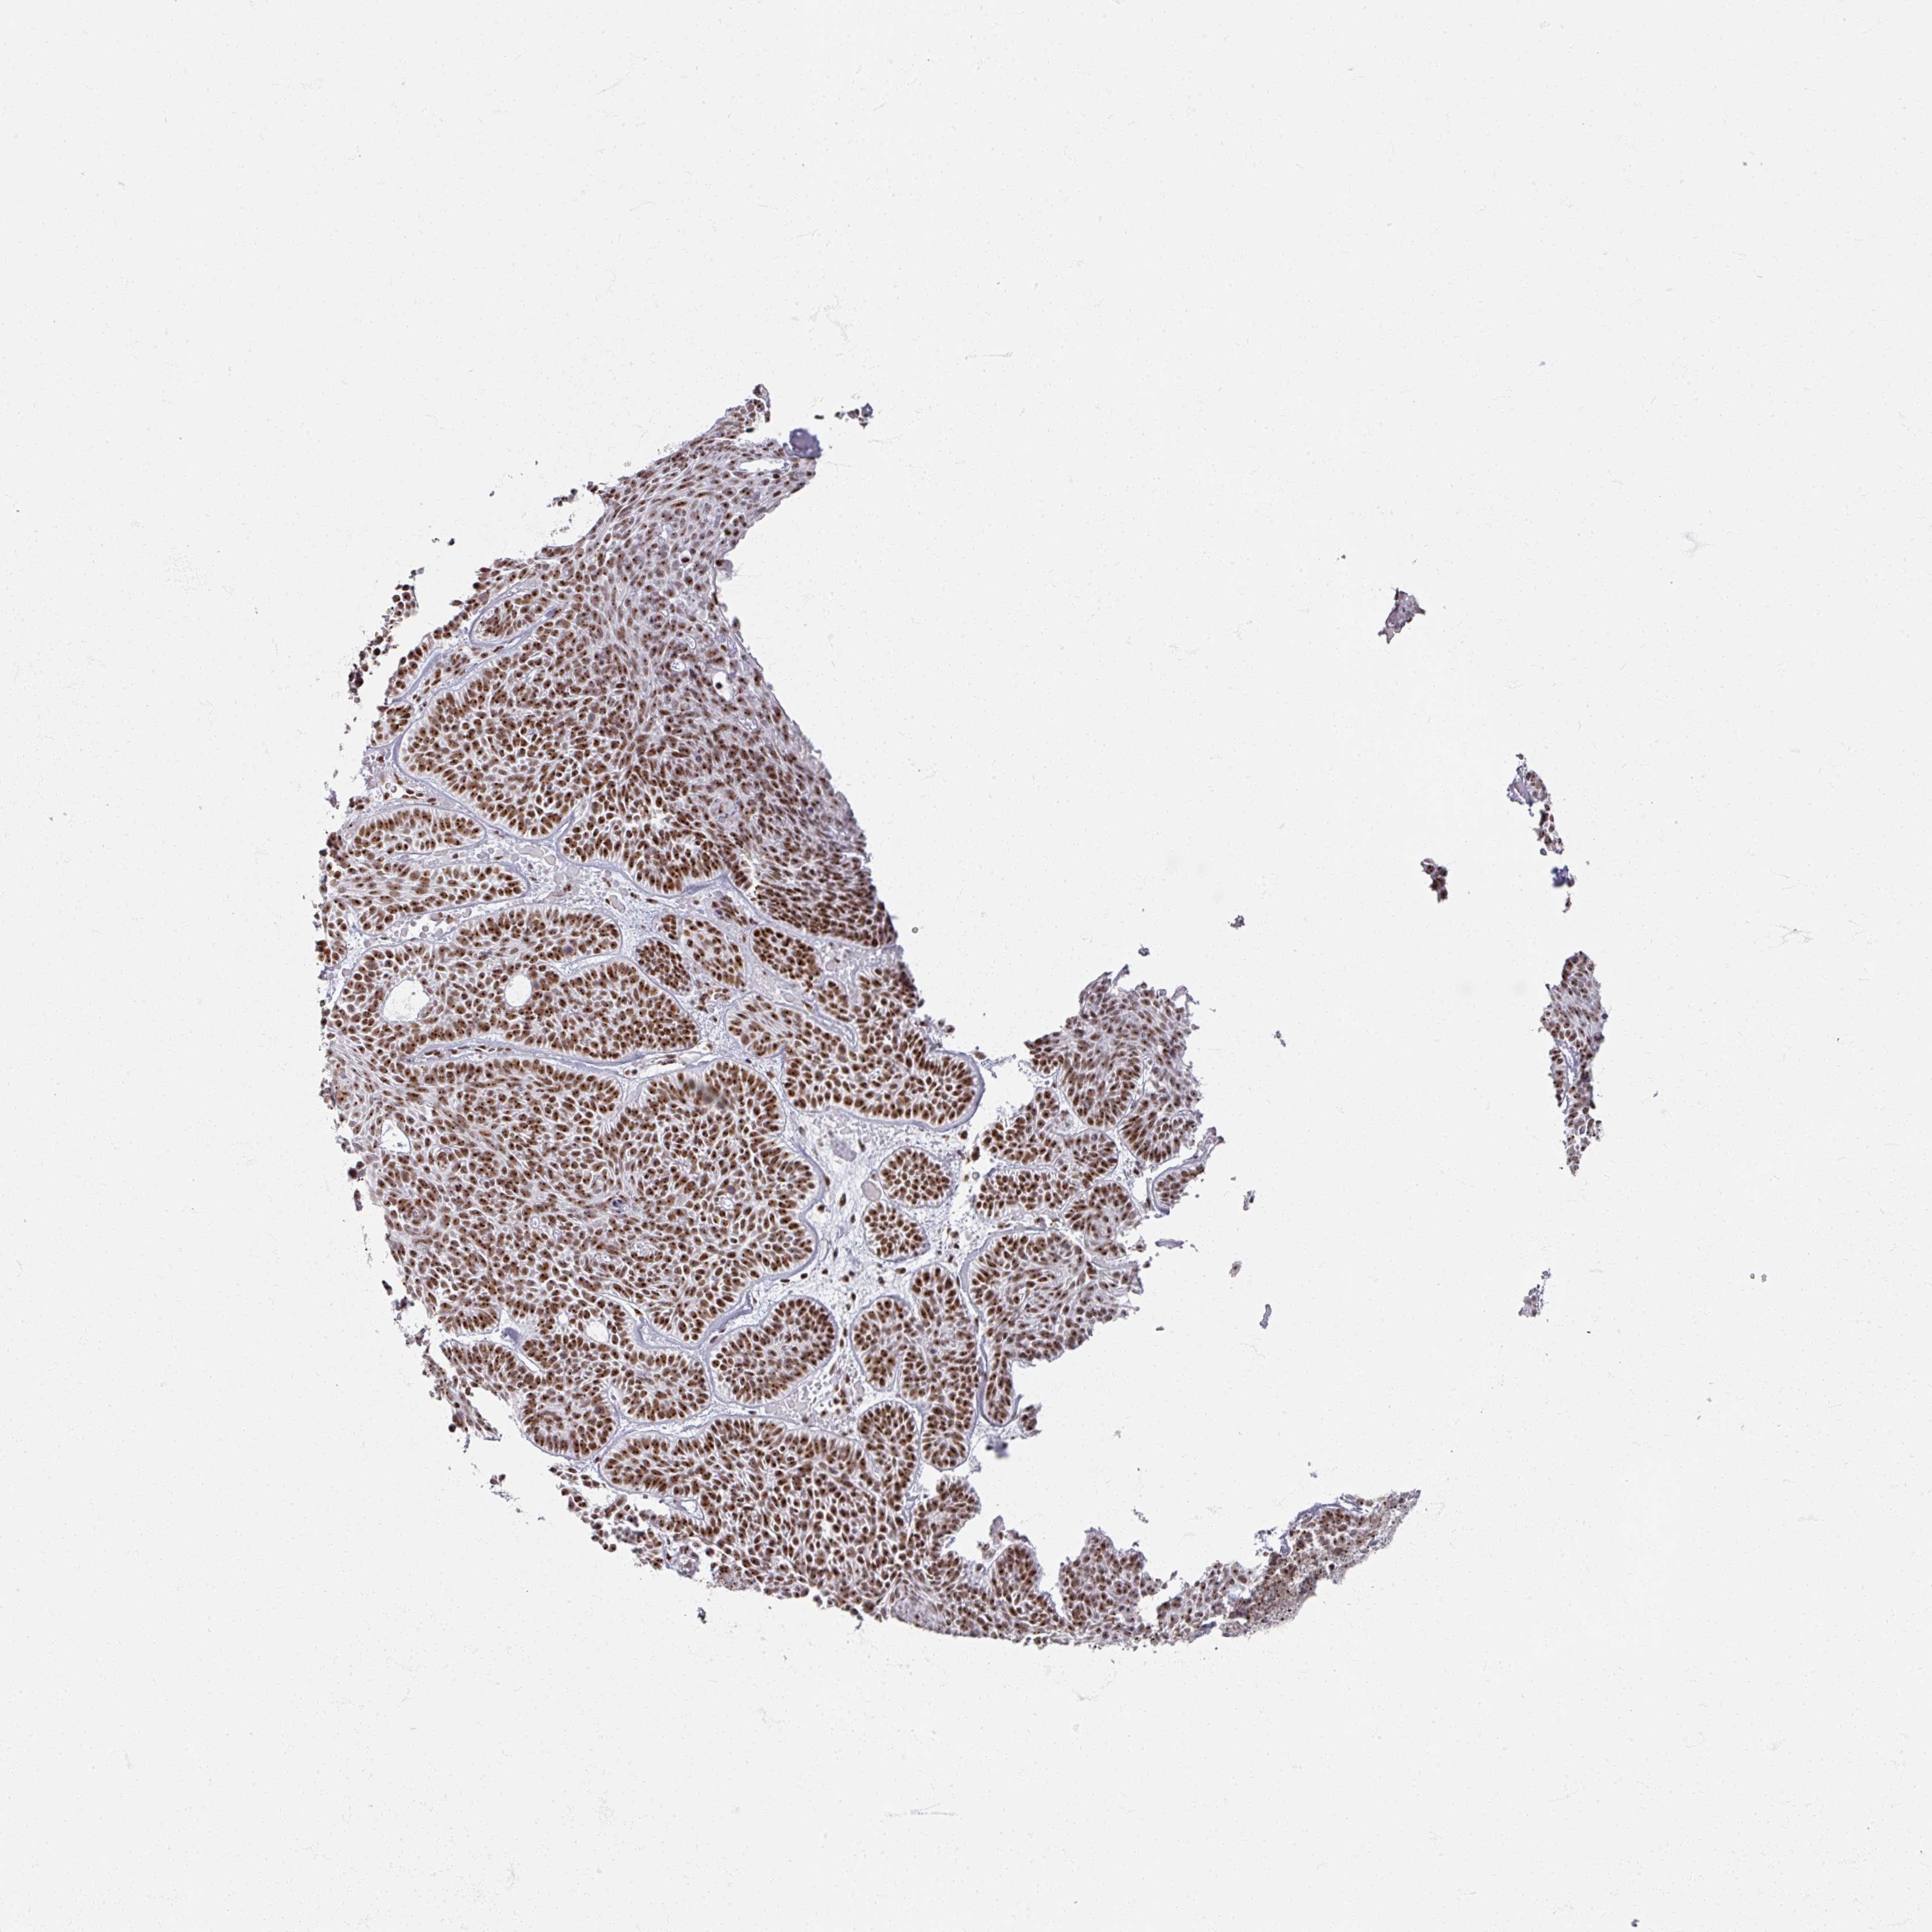

SKIN CANCER - Protein expressioni

A mouse-over function shows sample information and annotation data. Click on an image to view it in a full screen mode. Samples can be filtered based on level of antibody staining by selecting one or several of the following categories: high, medium, low and not detected. The assay and annotation is described here.

Each image is clickable and will lead to virtual microscopy that enables deeper exploration of all samples and also displays staining intensity scores, fraction scores and subcellular localization as well as patient and tissue information for each sample.

Antibody CAB056157

Staining

High

Medium

Low

Not detected

Intensity

Strong

Moderate

Weak

Negative

Quantity

>75%

75%-25%

<25%

None

Location

Nuclear

Cytoplasmic/membranous

Cytoplasmic/membranous,nuclear

Squamous cell carcinoma, NOS

Squamous cell carcinoma, metastatic, NOS